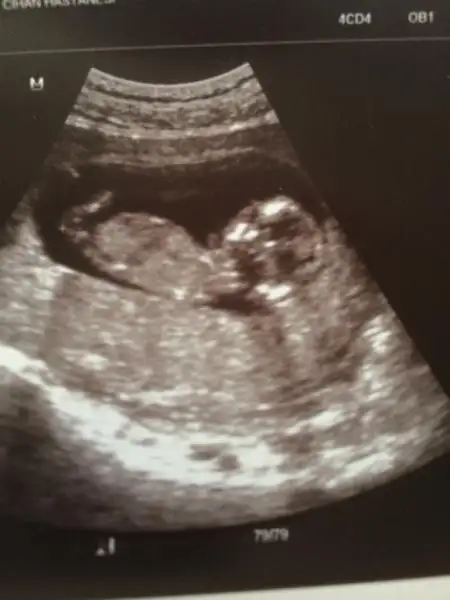

dr soylemeden siz gorun genital nub teorisi ( bebegin cinsiyeti)

Daha 20 gün var öğrenmemize sizin yorumlarınız neler acaba ??

6-8. Haftalarda ultrasondan 97% belli oluyo, ramzi theory diye internetten arastirin... bebek ultrasonda sağa tutunmussa erkek sola tutunmussa kizdi sanirim.

kızlar bizde burda 10+ haftalığız yinede şansımı denemek istedim çünkü çok merak ediyorum elimizdeki son ultrasnumuz bu 10 haftalıkken haftaya bayranmdan sonra gidicem blki bi tahminde bulunur doktor ama pek tahminde bulunacağını beklemiyorum açıkçası... :43::43:

gönderdiğim resimleri yorumlarmısınız 11+1 günlük fotolar. şimdiden teşekkürederim